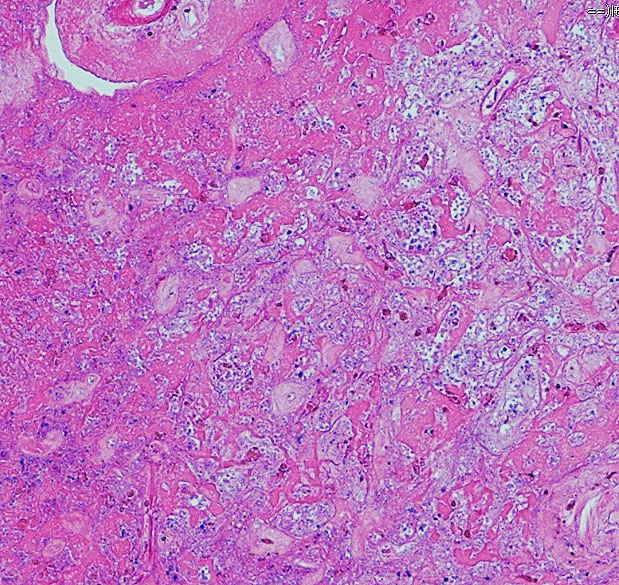

病理所見です

古い用語で凝固壊死 coagulation necrosisという言葉がもっとも適切に病理像を表しています。放射線による血管内皮のダメージで血管壁がヒアリン化して閉塞して虚血となります。また乏突起膠細胞がダメージをうけて髄鞘が脱落します(脱髄)。その結果,炎症と組織修復のための新生血管増殖が生じて脳間質組織浮腫が生じます。IL-1, TNF, IL-6などの炎症惹起性サイトカインはステロイドで抑えられます。同時に,この過程ではreactive astrocytesから多量のVEGFが産生されこれが放射線壊死による脳障害の主因と考えられています。VEGFは血管透過性 vascular permiabilityを増大させるので,組織間浮腫が高度なります。

左,壊死像と脳の境界領域。右,壊死層の中の大小の血管の閉塞像とマクロファージの浸潤がみられます。動脈壁のヒアリン化 hyaline thickening/hyalinizationと血管内腔の閉塞も特徴的な所見です。脳組織は中心部で虚血壊死になり,周囲組織での神経細胞のアポトーシスや白質変性も同時に進行します。この様な部位からの組織低酸素状態で誘発されるVEGFの産生と炎症惹起物質(TNF-alphaなどのサイトカイン)が,細血管からの血漿成分の漏出をまねき脳組織浮腫や慢性炎症を引き起こすと考えられています。fibrinoid deposition, fibrogliosisや微小石灰化の所見を伴うこともあります。

周囲の正常構造を保っている周囲脳組織内の反応性グリア細胞,豊富な好酸性胞体を有するreactive astrocyte(左下の赤い細胞)が多数見られます。 血管新生が盛んに生じていて拡張した毛細血管のような血管構造 telangiectasisが増加します。

放射線壊死の活動期は半年から2年くらいです。その後には脳壊死の部分が萎縮し周囲の脳浮腫は消褪します。組織学的には壊死巣は瘢痕組織となります。中心部は肉芽腫となり周囲にはgliofibrosisを残します。